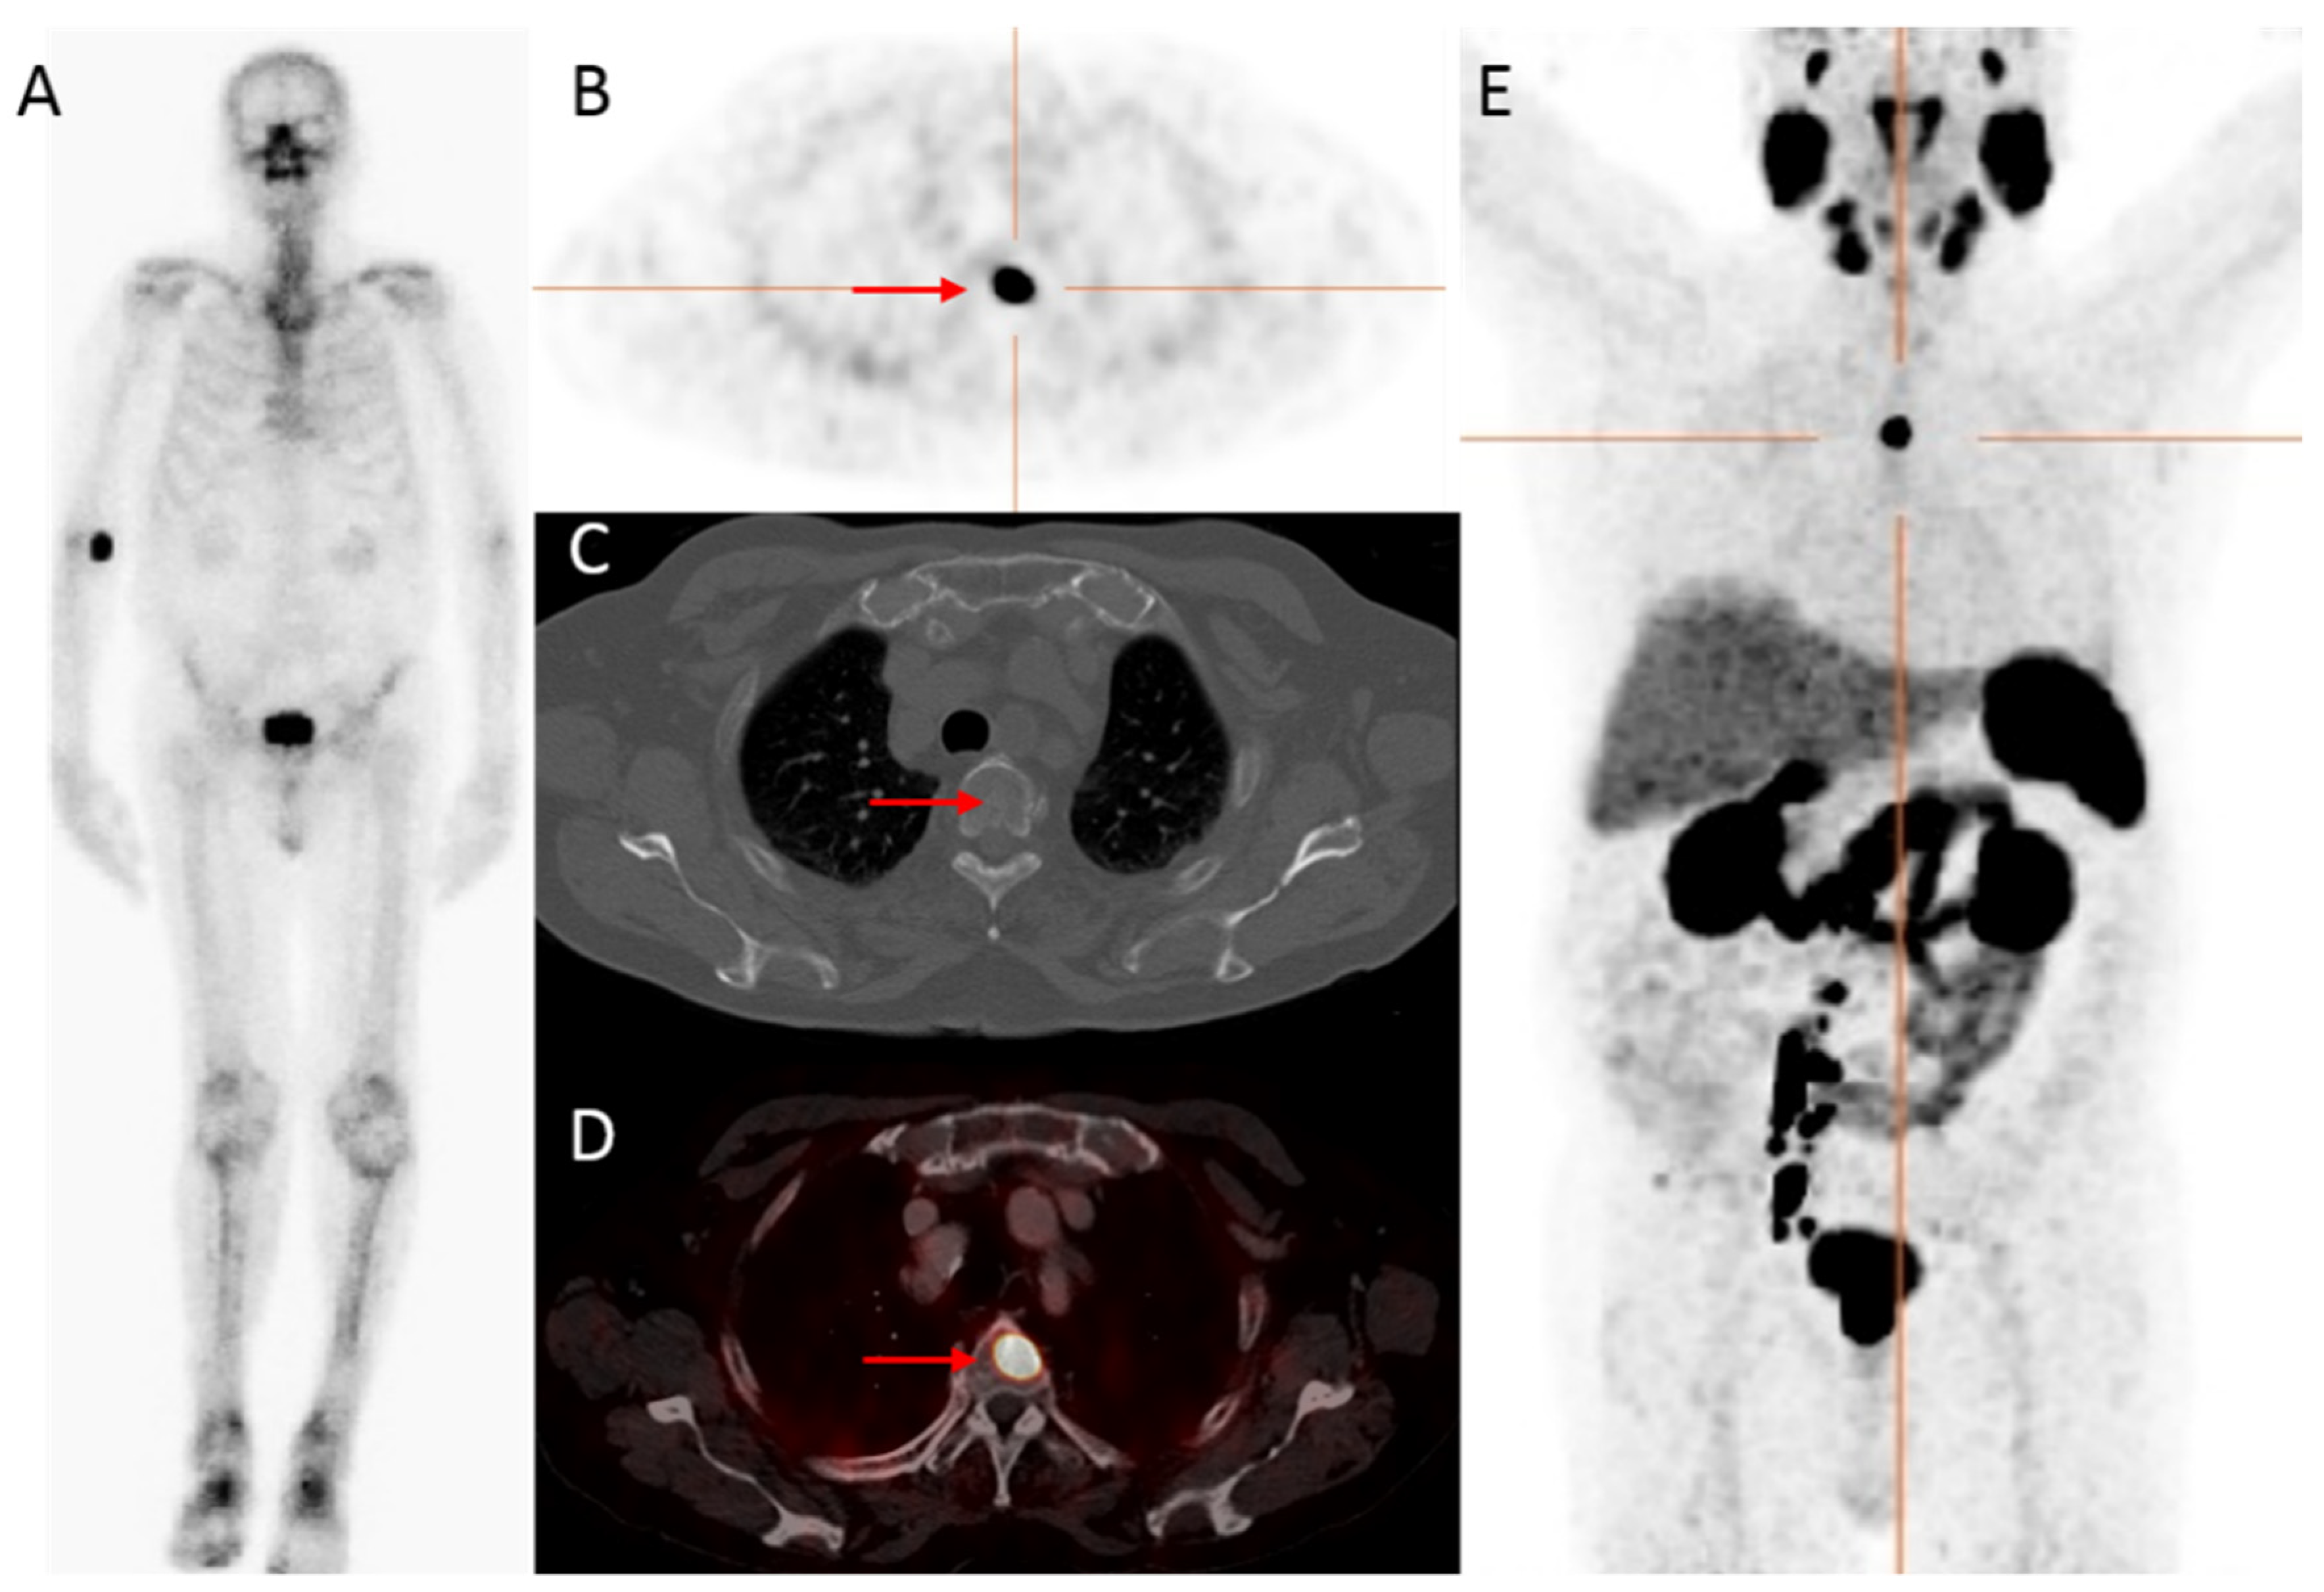

Figure 1.

An 83-year-old patient, with castration-resistant prostate cancer (CRPC) after initial treatment with hormonal therapy (2009), and secondary abiraterone (2019), showed improved detection of bone metastatic prostate cancer PCa with 68Ga-PSMA PET/CT compared to bone scintigraphy. The prostate—specific antigen (PSA)—value at PET scanning was 25.9 ng/mL. On the bone scintigraphy, no suspect bone metastases were visualized (A). Transversal 68Ga-PSMA PET (B), fused PET/CT (D) and maximum intensity projection (MIP) (E) revealed a lesion located in the thoracic spine with increased PSMA expression (red arrow), with no evident substrate on CT (C). Time interval between bone scintigraphy and 68Ga-PSMA PET/CT was 5 weeks.